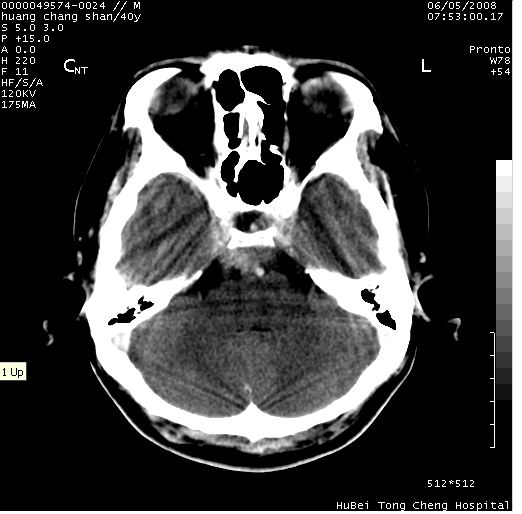

患者 m,40y。头痛,视力模糊,多饮多尿,性欲减退半年余。

行ct平扫+增强,图象如下:

结合临床考虑鞍上生殖细胞瘤可能性大于脑膜瘤(增强未见脑膜围征),建议结合冠状位扫描看病灶起源及垂体窝、鞍底情况。垂体窝内未见明显软组织密度影,垂体窝未见扩大,暂不考虑垂体瘤;病灶较大,未见囊变及钙化,颅咽管瘤不支持。期待结果!

2、ct表现:肿瘤呈类圆形,均匀略高密度,无囊变,无钙化。侧脑室有扩大。

4、鉴别诊断:脑膜瘤,瘤体内点状钙化最具特征性,常位于鞍结节。颅咽管瘤,蛋壳样钙化,常有囊变。动脉瘤,位于鞍旁,强化与动脉一致。有时尚需与发生于鞍区的生殖细胞瘤鉴别,生殖细胞瘤钙化亦较常见。